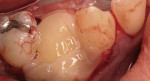

Severe facial abfraction lesions were present on the facial surfaces of teeth Nos. 28 to 30, associated with temperature sensitivity and food impaction (Figure 13). A full split-thickness facial flap was elevated with no vertical releasing incisions. A high-speed rotary instrument13 was used to reduce the buccal contours and eliminate the notching (Figure 14) in the affected areas. Removal of the smear layer and surface demineralization to expose collagen fibers was accomplished with the use of a tetracycline slurry paste. After thorough removal of this treatment, the root surfaces were treated with Emdogain. Alveolar defects were grafted with a mixture of anorganic bovine bone mineral (Bio-Oss®, Osteohealth® Company, www.osteohealth.com). The area was covered with a 10-mm x 30-mm piece of bilayer porcine collagen (Mucograft®, Osteohealth Company) soaked in the liquid expressed from PRF clots placed in the PRF box (Figure 15 and Figure 16). The collagen was then covered with a PRF membrane, and the vestibular flap was repositioned to the crown margins and CEJ (Figure 17). The sutures were removed at 2 weeks. The image shown is 8-week healing with an excellent soft-tissue response (Figure 18).